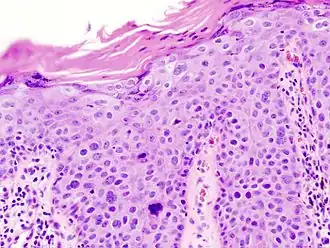

Histopathologically, the epidermis in SCC in situ (Bowen’s disease) will show hyperkeratosis and parakeratosis. There will also be marked acanthosis with elongation and thickening of the rete ridges. These changes will overly keratinocytic cells which are often highly atypical and may in fact have a more unusual appearance than invasive SCC. The atypia spans the full thickness of the epidermis, with the keratinocytes demonstrating intense mitotic activity, pleomorphism, and greatly enlarged nuclei. They will also show a loss of maturity and polarity, giving the epidermis a disordered or “windblown” appearance.

Two types of multinucleated cells may be seen: the first will present as a multinucleated giant cell, and the second will appear as a dyskeratotic cell engulfed in the cytoplasm of a keratinocyte. Occasionally, cells of the upper epidermis will undergo vacuolization, demonstrating an abundant and strongly eosinophilic cytoplasm. There may be a mild to moderate lymphohistiocytic infiltrate detected in the upper dermis.[33]

In situ disease

Bowen's disease is essentially equivalent to and used interchangeably with SCC in situ, when not having invaded through the basement membrane.[33] Depending on source, it is classified as precancerous[34] or SCC in situ (technically cancerous but non-invasive).[35][36] In SCC in situ (Bowen's disease), atypical squamous cells proliferate through the whole thickness of the epidermis.[33] The entire tumor is confined to the epidermis and does not invade into the dermis.[33] The cells are often highly atypical under the microscope, and may in fact look more unusual than the cells of some invasive squamous cell carcinomas.[33]

SCC in situ, high magnification, demonstrating an intact basement membrane.[33] -